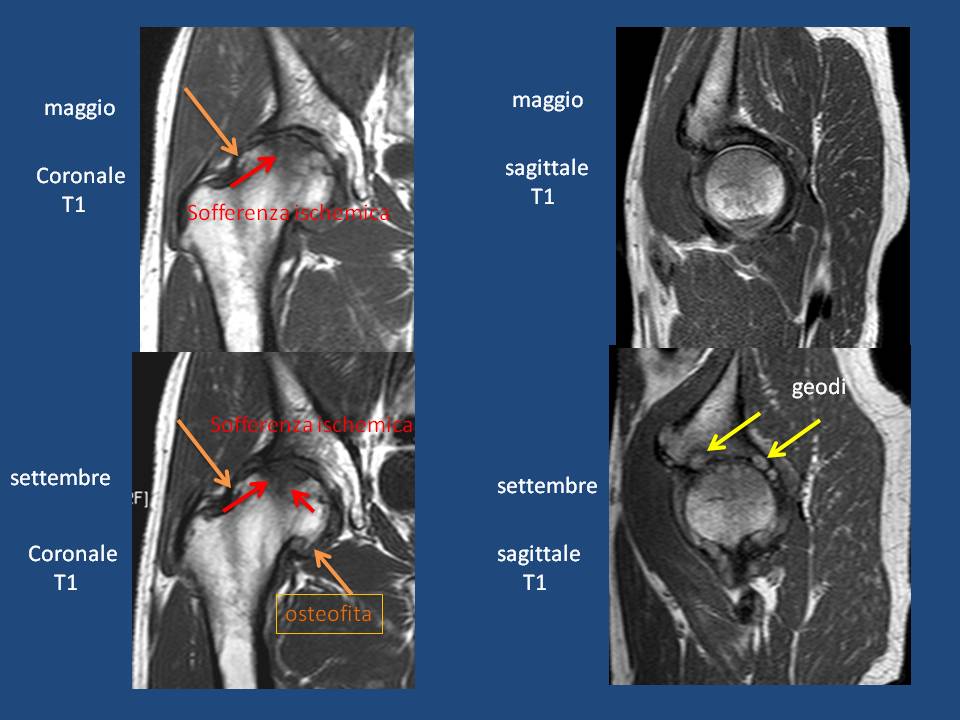

Nella sottostante diapositiva si nota la perdita della sfericità della superficie articolare femorale, la sofefrenza ischemica sub-condrale a distribuzione segmentale, con tipica morfologia triangolare con apice rivolto verso il centro della testa, ancora con sfumata interfaccia di separazione con l'osso sano; 4 mesi più tardi si documenta l'evoluzione dei processi ischemici verso lo stadio IV caratterizzati da netta delimetazione dell'area ischemica e dalla frammentazione degli stati sub-condrali con conseguente formazione di lacune geodiche.